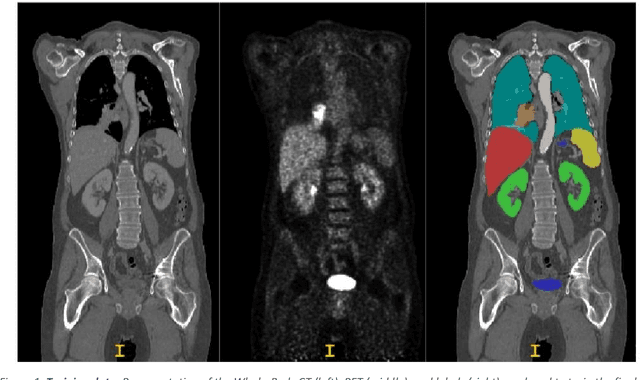

Abstract:Automatic segmentation of lesions in FDG-18 Whole Body (WB) PET/CT scans using deep learning models is instrumental for determining treatment response, optimizing dosimetry, and advancing theranostic applications in oncology. However, the presence of organs with elevated radiotracer uptake, such as the liver, spleen, brain, and bladder, often leads to challenges, as these regions are often misidentified as lesions by deep learning models. To address this issue, we propose a novel approach of segmenting both organs and lesions, aiming to enhance the performance of automatic lesion segmentation methods. In this study, we assessed the effectiveness of our proposed method using the AutoPET II challenge dataset, which comprises 1014 subjects. We evaluated the impact of inclusion of additional labels and data in the segmentation performance of the model. In addition to the expert-annotated lesion labels, we introduced eight additional labels for organs, including the liver, kidneys, urinary bladder, spleen, lung, brain, heart, and stomach. These labels were integrated into the dataset, and a 3D UNET model was trained within the nnUNet framework. Our results demonstrate that our method achieved the top ranking in the held-out test dataset, underscoring the potential of this approach to significantly improve lesion segmentation accuracy in FDG-18 Whole-Body PET/CT scans, ultimately benefiting cancer patients and advancing clinical practice.

Abstract:The Image Data Commons (IDC) contains publicly available cancer radiology datasets that could be pertinent to the research and development of advanced imaging tools and algorithms. However, the full extent of its research capabilities is limited by the fact that these datasets have few, if any, annotations associated with them. Through this study with the AI in Medical Imaging (AIMI) initiative a significant contribution, in the form of AI-generated annotations, was made to provide 11 distinct medical imaging collections from the IDC with annotations. These collections included computed tomography (CT), magnetic resonance imaging (MRI), and positron emission tomography (PET) imaging modalities. The main focus of these annotations were in the chest, breast, kidneys, prostate, and liver. Both publicly available and novel AI algorithms were adopted and further developed using open-sourced data coupled with expert annotations to create the AI-generated annotations. A portion of the AI annotations were reviewed and corrected by a radiologist to assess the AI models' performances. Both the AI's and the radiologist's annotations conformed to DICOM standards for seamless integration into the IDC collections as third-party analyses. This study further cements the well-documented notion that expansive publicly accessible datasets, in the field of cancer imaging, coupled with AI will aid in increased accessibility as well as reliability for further research and development.